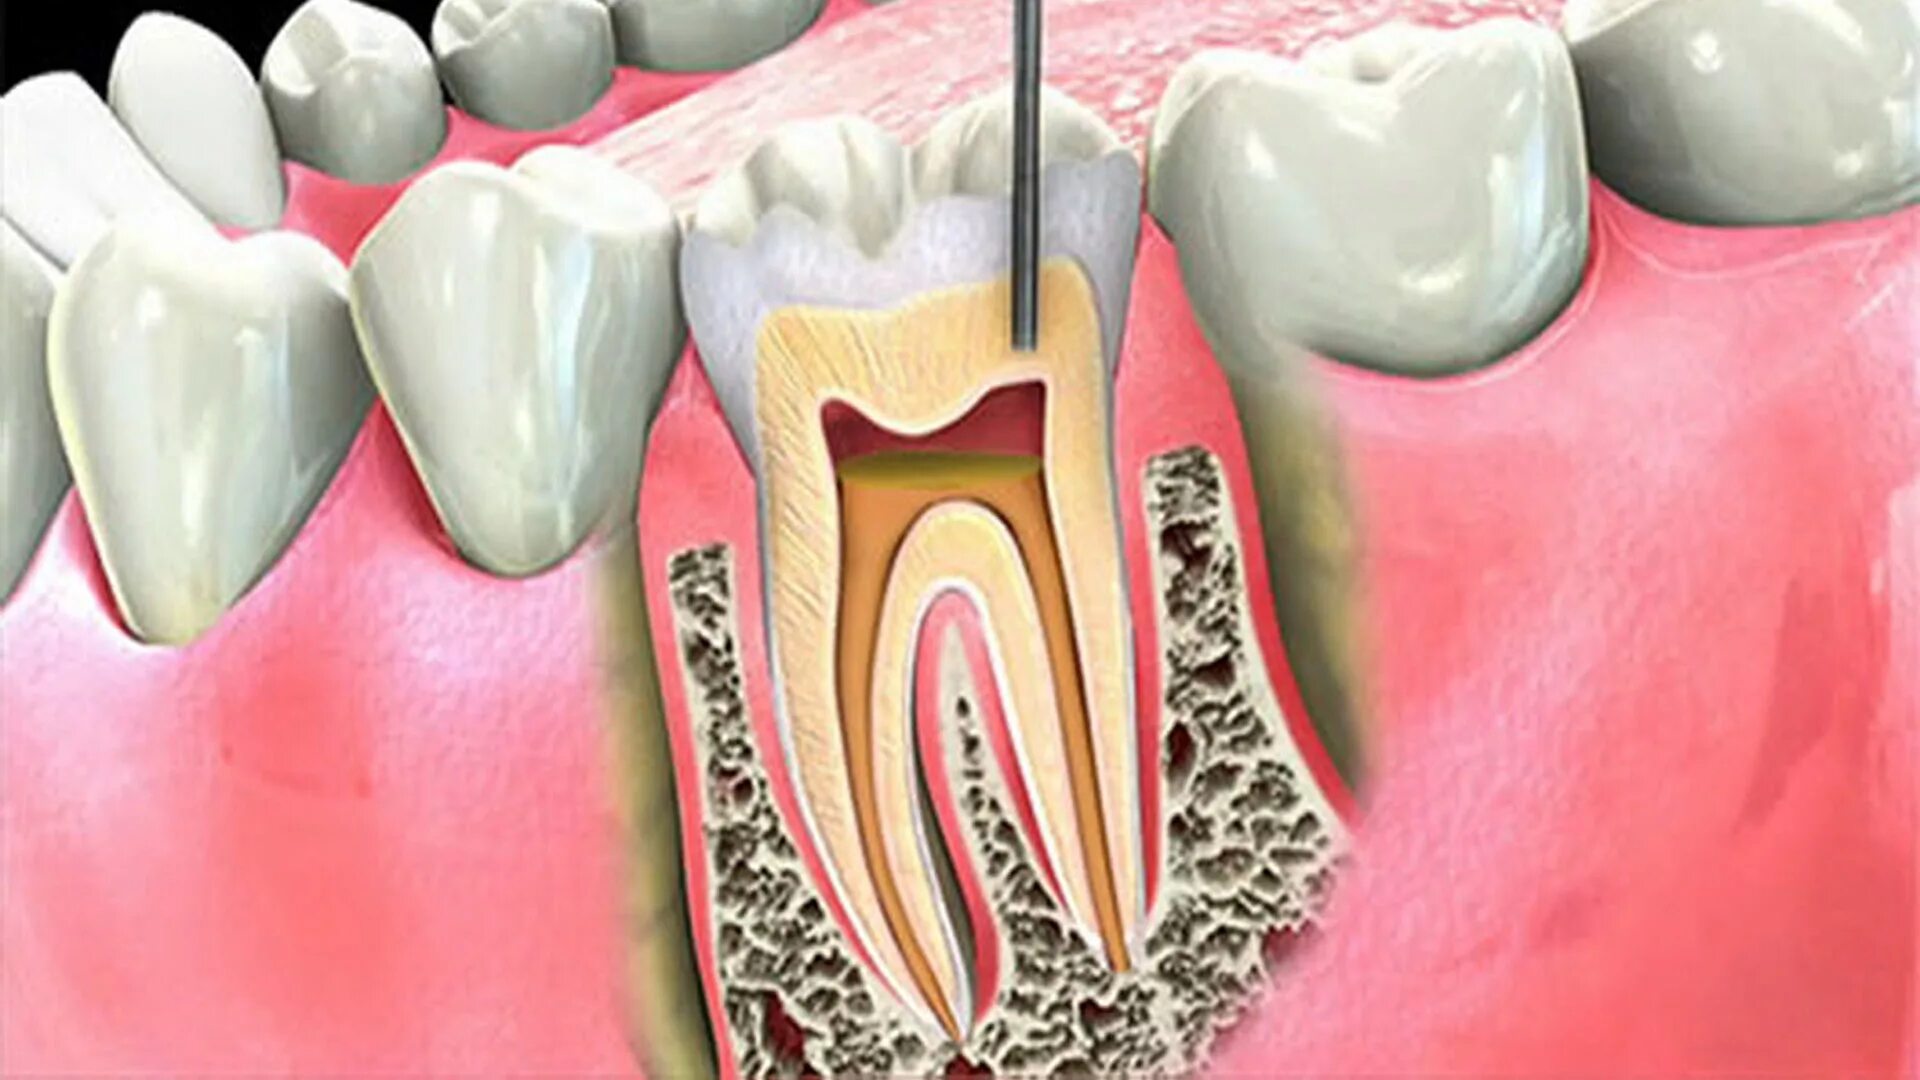

Воспаление зуба после удаления нерва